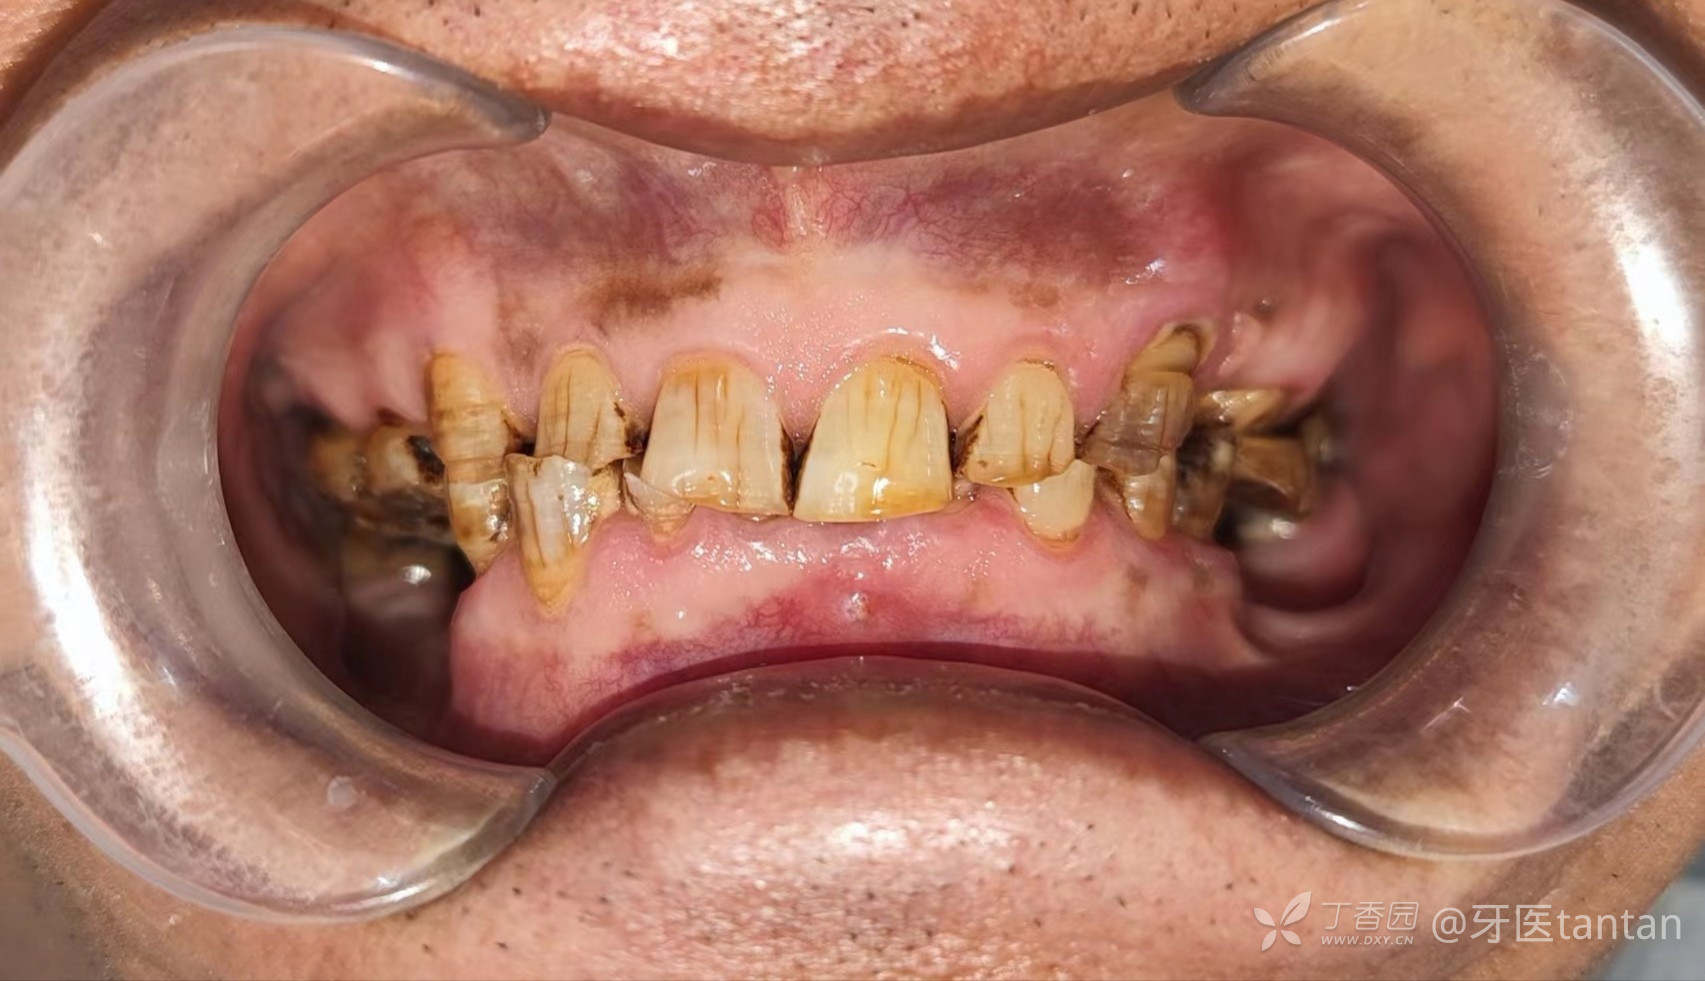

【初诊口内照】

正面观。严重深覆颌。

下前牙残根,见瘘管。